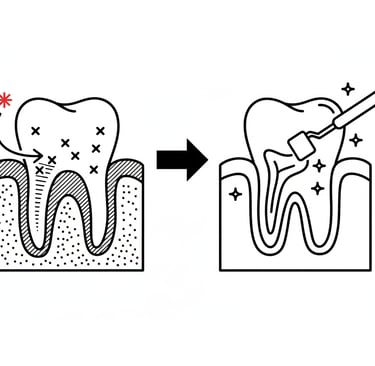

Ενδοδοντική θεραπεία (Απονεύρωση)

Η ενδοδοντική θεραπεία επεμβαίνει στο εσωτερικό του δοντιού (τον πολφό), όπου βρίσκονται νεύρα και αγγεία. Σκοπός της είναι να αφαιρεθεί ο μολυσμένος ή φλεγμονώδης ιστός, να καθαριστούν και να σφραγιστούν οι ριζικοί σωλήνες, ώστε να σωθεί το δόντι και να εξαλειφθεί ο πόνος ή η λοίμωξη.